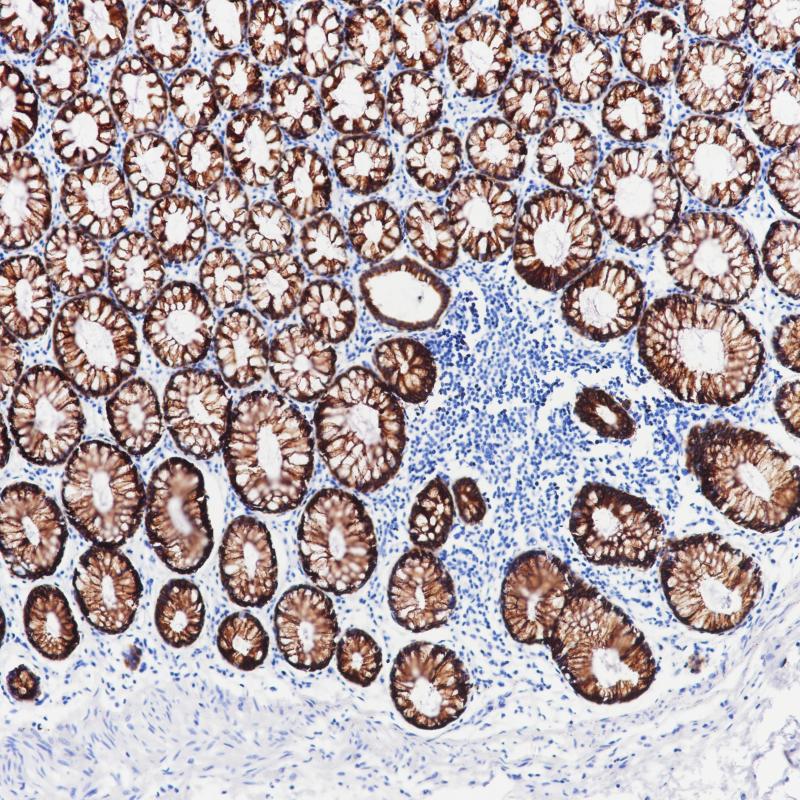

Cytokeratin 8&18 Cocktail

细胞角蛋白8&18表达于所有单层上皮,尤其是各种腺上皮。 该抗体能够识别50及43kDa的低分子量角蛋白,对应的Moll分类为CK8与CK18,主要用于鉴别诊断鳞癌与腺癌

阳性对照

结肠

亚细胞定位

细胞质